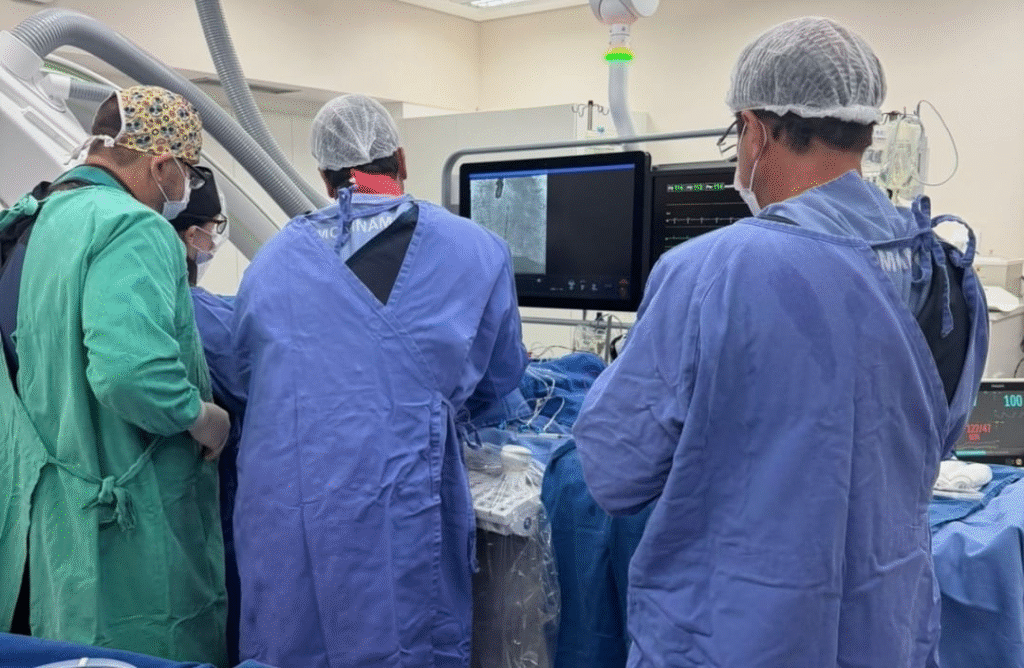

O procedimento contou com a atuação de um “Heart Team”, uma equipe multidisciplinar essencial para intervenções cardíacas dessa complexidade, reunindo profissionais de diferentes especialidades.

Integraram a equipe os cardiologistas intervencionistas, Ricardo José Tofano e Marielle Rodrigues Martins, os cirurgiões cardíacos Sideral Ferreira Alves e Diego Gaia, o ecocardiografista Marcelo Peron e o anestesista José Luiz.

Para o Dr. Tofano, a atuação conjunta foi decisiva para o resultado positivo.

“Nenhum procedimento como esse é feito de forma isolada. Ele depende de um Heart Team completo, experiente e bem alinhado. Cada profissional tem um papel fundamental, desde a avaliação inicial até o acompanhamento pós-procedimento. Esse trabalho em equipe é o que garante segurança e excelência ao paciente”, finaliza.